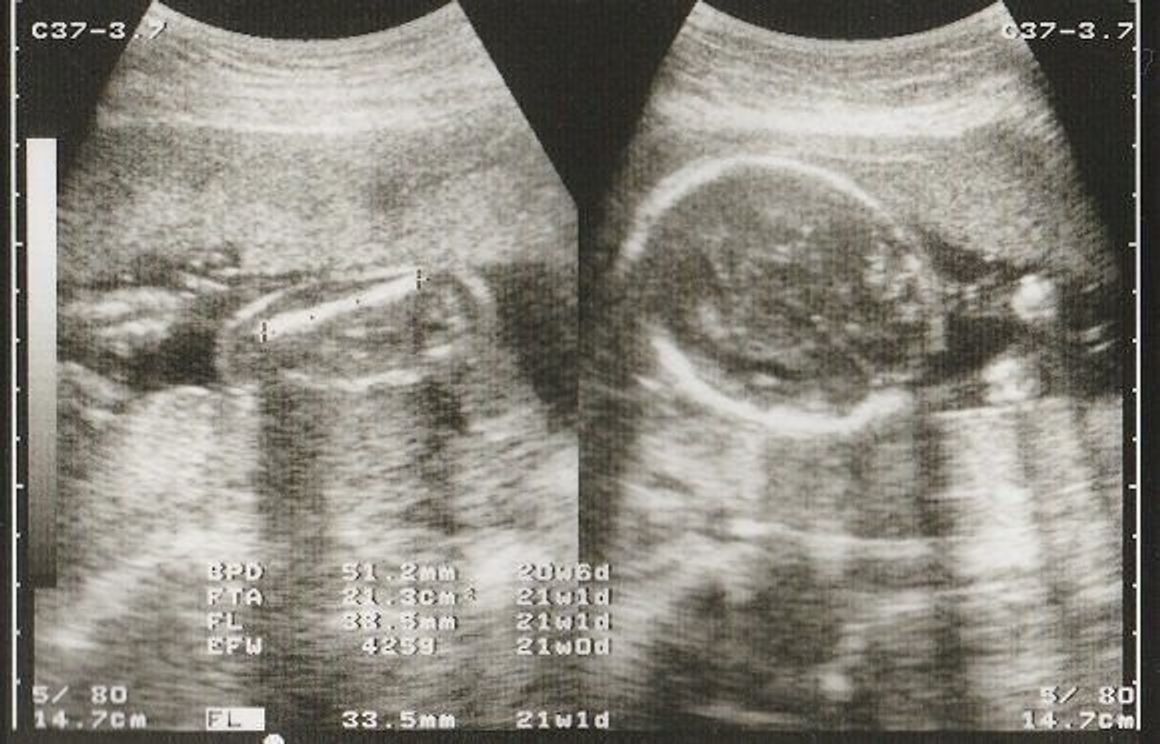

21週 赤ちゃん 何してるのギャラリー

各画像をクリックすると、ダウンロードまたは拡大表示できます

![]() 妊娠21週目 21w0d 6d のエコー写真とエピソード 妊娠6ヶ月 Cozre コズレ 子育てマガジン | ![]() 妊娠21週目 21w0d 6d のエコー写真とエピソード 妊娠6ヶ月 Cozre コズレ 子育てマガジン | ![]() 妊娠21週目 21w0d 6d のエコー写真とエピソード 妊娠6ヶ月 Cozre コズレ 子育てマガジン |